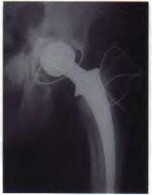

Figure 6 shows the radiograph of a 72-year-old woman who underwent a primary total hip arthroplasty

17 years ago. She now reports groin pain. Optimal surgical management should consist of which of the following?

Polyethylene wear is evident due to the superiorly eccentric position of the femoral head within the acetabulum. Despite proximal femoral osteolysis, the component appears well fixed, as does the acetabulum. The acetabular component appears to be well positioned. Therefore, an isolated synovectomy and polyethylene liner exchange is indicated. If the hip is stable, there is no need for more extensive revision work.

REFERENCE: Barrack RL, Booth RE Jr, Lonner JH, et al (eds): Orthopaedic Knowledge Update: Hip and Knee Reconstruction 3. Rosemont, IL, American Academy of Orthopaedic Surgeons, 2006, pp 521-528.